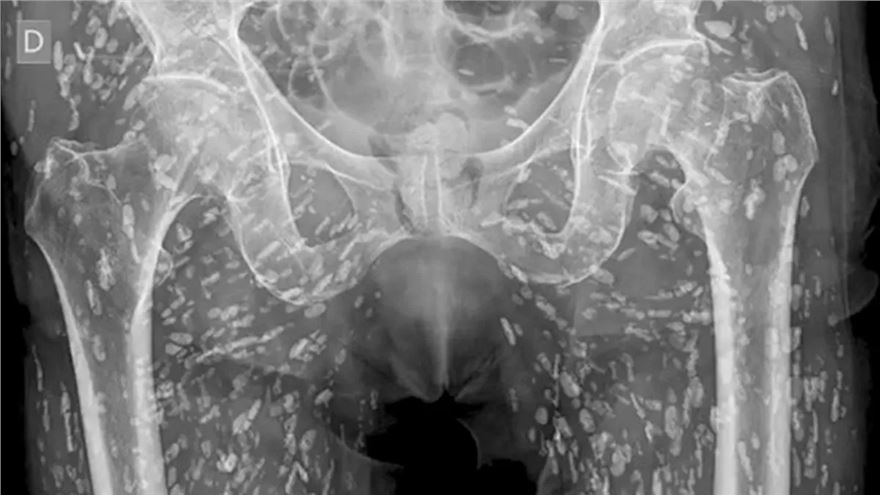

近日,美国佛罗里达大学急诊医学助理教授萨姆·加利,发布了一组令人震惊的X光片,显示一名男子因烹饪时犯下严重错误,导致体内感染绦虫,遍布钙化虫卵。加利医生在社交媒体上分享了这一病例,称其为“见过最疯狂的X光片之一”。

加利医生介绍,这名男子因食用未煮熟的猪肉,导致猪带绦虫的幼虫囊尾蚴在体内寄生,并在骨盆周围的软组织中留下大量虫卵。这些虫卵在X光片上呈现为小白点,遍布男子下半身。

囊尾蚴病可由猪带绦虫的幼虫囊尾蚴引起,可遍布全身,主要集中于臀部和腿部的肌肉和软组织。加利医生警告称,如果囊尾蚴游走到大脑并在那里停留,会导致头痛、意识混乱、癫痫发作甚至死亡等严重神经症状。